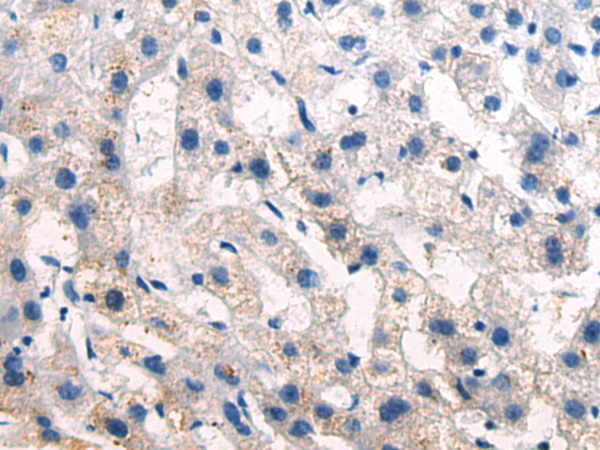

分类: 科研抗体货号: P05998别名: PYM; WIBG应用: IHC反应种属: Human, Mouse